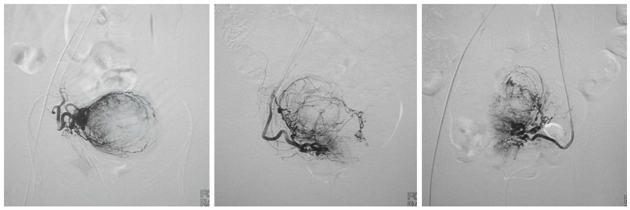

三位患者在妇科入院后接受了全面检查,通过院内多学科诊疗团队(MDT)进行全面、细致的评估,同时结合患者及家属意愿,选择行“子宫动脉介入栓塞术(UAE)”,由我院介入治疗专家高国明主任医师带领妇科团队制定个性化介入治疗方案并顺利实施。术中,在医学影像设备的引导下,通过患者大腿根部约2mm的穿刺点局麻后,将极细的导管精准地插入子宫动脉,注入栓塞材料,阻断子宫肌瘤的血液供应,使其“原位灭活”,肌瘤逐渐萎缩、吸收,达到治疗目的。介入手术患者全程清醒无痛苦、创伤小、恢复快,避免了传统外科手术创伤及术后并发症,既保留了育龄女性子宫功能和正常生育能力,又促进家庭关系稳定和谐,保护了中老年女性盆腔脏器功能,为患者提供了更高水平、更高质量、更高效率的医疗服务,全方位、全生命周期保障妇女健康。术后,三位患者各项生命体征平稳,恢复良好,对治疗效果十分满意。